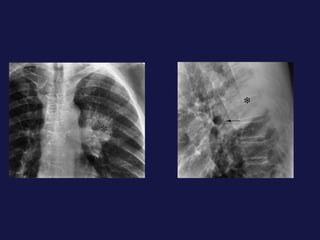

Hallazgos radiológicos. Tumor periférico. Nódulo o masa pulmonar. Bordes definidos, lobulados, irregulares, espiculados Calcificación ( focal, excéntrica ) Cavitación 1% presentan nódulos satélites. 25%  de broncoalveolares son múltiples. Adenocarcinoma y carcinoma de células alveolares.

Hallazgos radiológicos. Tumorperiférico. Nódulo o masa pulmonar. Bordes definidos, lobulados, irregulares, espiculados Calcificación ( focal, excéntrica ) Cavitación 1% presentan nódulos satélites. 25% de broncoalveolares son múltiples. Adenocarcinoma y carcinoma de células alveolares.